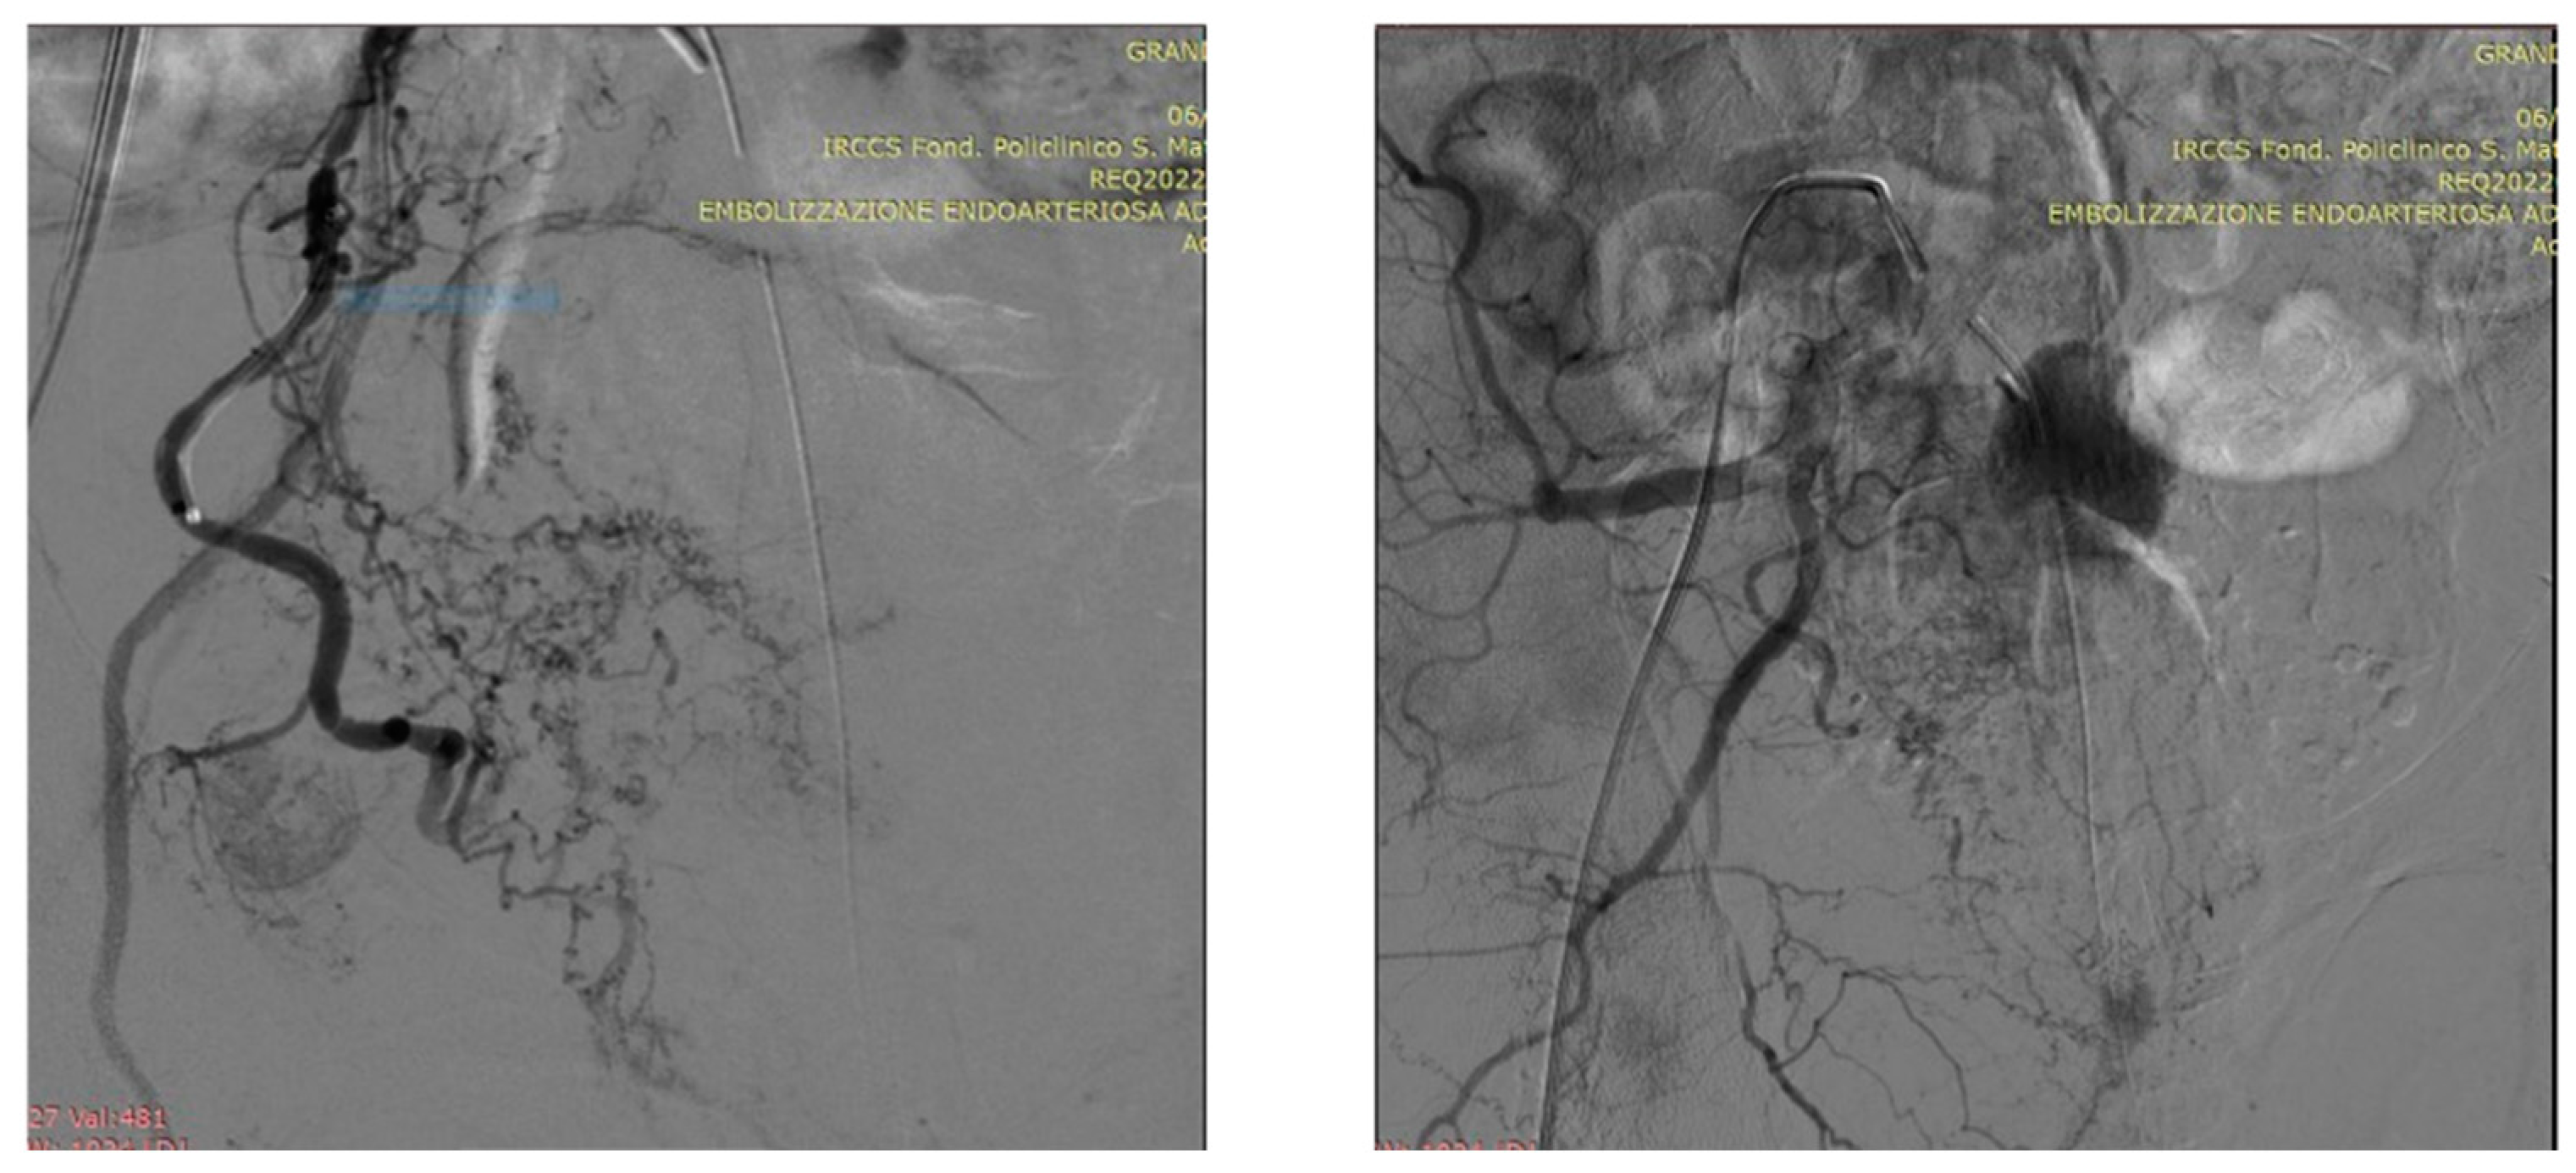

5.1. Technical details of PAE